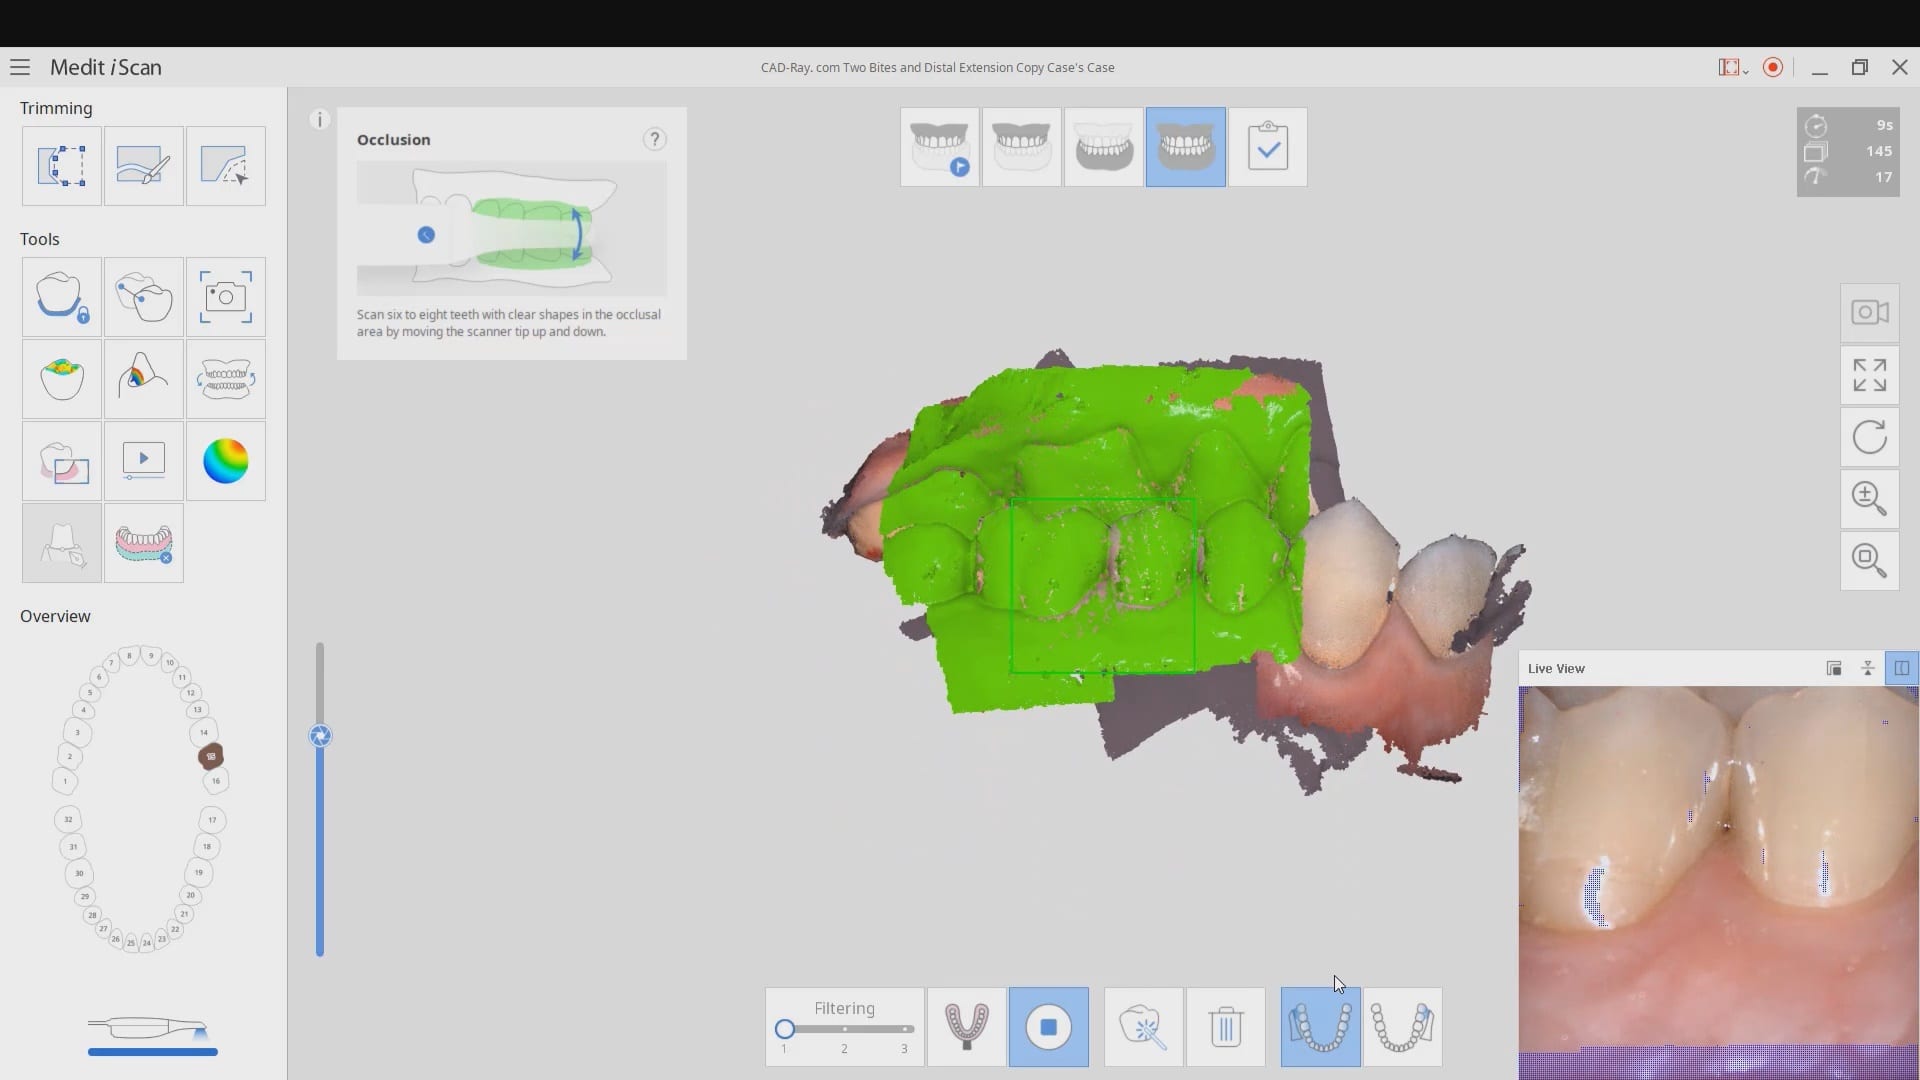

Distal Extension Second Molar Crown Replacement in Copy Mode and With Two Bites

October 28, 2019Every distal extension case I have to accomplish the following: take two bites to make sure my vertical dimension does not change with pre-op and prep images make sure I […]